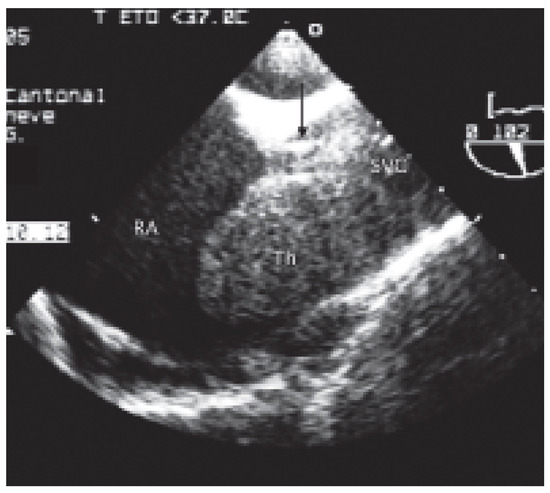

Valve Prosthesis in the Tricuspid Position: An Useasy Relationship

by P. Trigo Trindade, J. Sierra and C. Vuille

Cardiovasc. Med. 2006, 9(4), 167; https://doi.org/10.4414/cvm.2006.01163 - 28 Apr 2006

Case report. A27-year-old woman from Madagascar was referred to our institution because of right heart failure [...] Full article